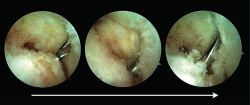

Una vez que el tendón es seccionado, se externaliza a través del portal endoscópico posteromedial para pasarle una sutura que permita la tracción tendinosa. Se recomienda realizar una sutura de Krackow con un hilo de alta resistencia (Figura 4).

Figura 4. El tendón del músculo flexor hallucis longus (FHL) es externalizado por el portal posteromedial y se realiza una sutura de Krackow con un hilo de alta resistencia.

El tendón del FHL debe entonces insertarse en el calcáneo a través de un túnel. La ubicación deseable para el túnel calcáneo debe ser en el borde más posterosuperior del tubérculo calcáneo. Para localizar este punto es de ayuda la utilización de una aguja de Kirschner que se introduce a través del portal posteromedial. La aguja de Kirschner se utiliza como guía para la broca y es recomendable que tenga un ojal en el extremo romo. La aguja debe alcanzar el hueso calcáneo, localizar el punto idóneo para el túnel y penetrar el calcáneo en dirección dorsal-medial a plantar-lateral.

Figura 5. El túnel calcáneo para la transferencia del tendón del flexor hallucis longus (FHL) se localiza en el borde más posterosuperior del tubérculo calcáneo. El punto exacto del túnel se localiza con una aguja de Kirschner introducida a través del portal posteromedial. Una broca canulada se introduce a través de la aguja de Kirschner para realizar el túnel calcáneo.

El diámetro adecuado del túnel depende del diámetro del tendón FHL, que se mide una vez externalizado y tras ser seccionado. La longitud del túnel debe ser al menos de 10 a 15 mm más larga que la longitud ideal del tendón FHL. Usualmente, un túnel mínimo de 30 mm de longitud debería ser suficiente, pero debe considerarse la longitud de tendón exterior al túnel (Figura 5). Una vez realizado el túnel y aún con la aguja guía transfixiando el calcáneo, se introducen las suturas en el ojal de la aguja de Kirschner. Al empujar la aguja de Kirschner desde su salida en la zona plantar, las suturas pasan a través del túnel hasta la región plantar. A continuación, al traccionar de las suturas, el tendón se introducirá en el túnel (Figura 6).

Figura 6. Tras realizar el túnel calcáneo, se carga la aguja de Kirschner con las suturas de Krackow realizadas sobre el tendón. A continuación, la aguja de Kirschner es traccionada desde su salida en la zona plantar, de modo que el tendón del músculo flexor hallucis longus (FHL) se introduce en el túnel calcáneo.